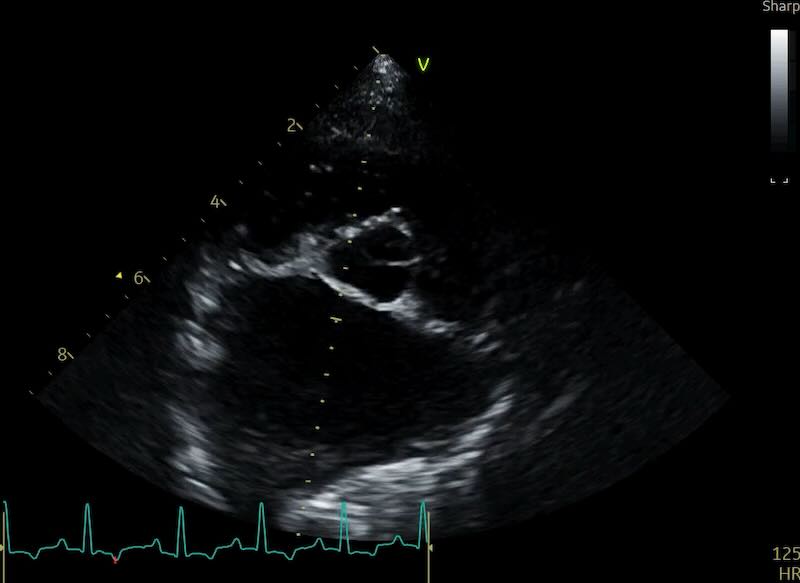

Here are 2 examples of a normal LA with a pulmonary vein, and a very enlarged LA also having pulmonary vein issues:

The Clinical Workaround: If you see a vein entering the atrium, do not measure into the vessel. There are multiple described approaches for coping with this, and as yet no consensus on the best approach:

- Option 1: “approximate” the atrial border by connecting the visible edges of the atrium with an imaginary curved line that follows the natural contour of the chamber. If the dropout is so severe that you are guessing, it is time to move to a different view.

- Option 2: Angle your measure to the little ‘bump’ that sits just to the right of the vein.

- Option 3: Angle your measure to the wall where it first becomes visible to the left of the vein

Personally, I’m a fan of option 2. But set guidelines if published will maybe solve this debate for good…